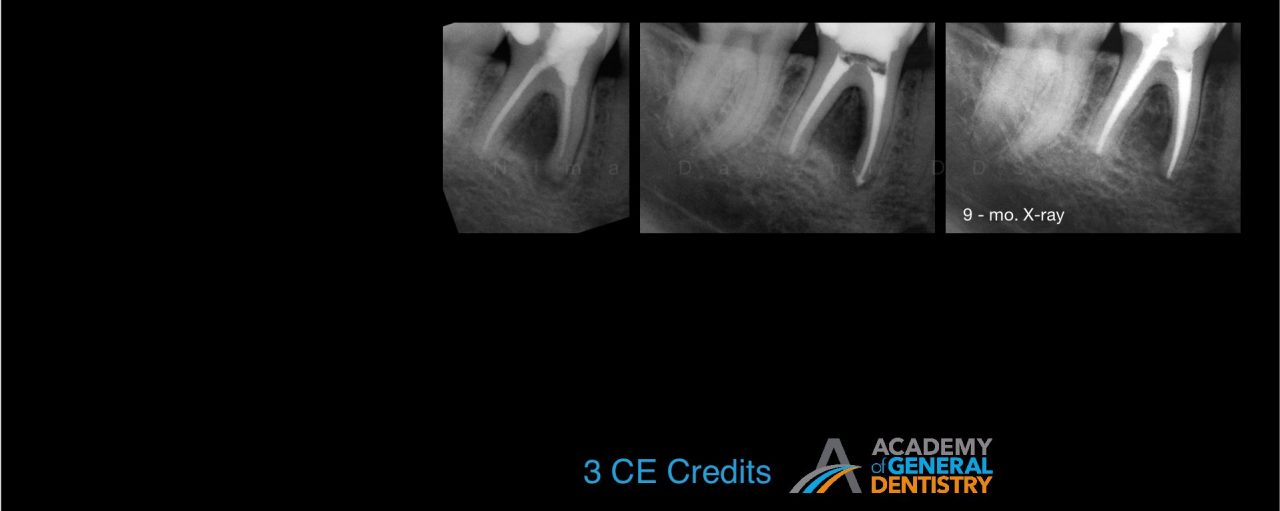

According to literature, the survival rate of endodontically treated teeth is close to 98%. How do we update our understanding of endodontics so that we can care for our patients and close in on the 98% published survival rate? The most common reason for a failed root canal treatment is inadequate treatment. However, there are some cases in which a root canal treatment is carried out in accordance with the highest standards, and yet still results in failure. In most such cases, the endodontic failure results from persistent intra-radicular infection. In other cases, extra-radicular infections and intrinsic or extrinsic non-microbial factors might be implicated in the failure.

The purpose of this lecture is to discuss the etiological factors of failed root canal treatments using a series of clinical cases. It will aid clinicians in choosing between surgical and non-surgical management of a failed root canal in an evidence-based manner. Indications for the non-surgical vs. surgical retreatment of failed endodontic cases are discussed in order to maximize the success of an endodontic retreatment.